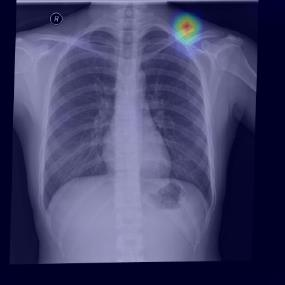

Chest X-ray (CXR) is the most typical diagnostic X-ray examination for screening various thoracic diseases. Automatically localizing lesions from CXR is promising for alleviating radiologists' reading burden. However, CXR datasets are often with massive image-level annotations and scarce lesion-level annotations, and more often, without annotations. Thus far, unifying different supervision granularities to develop thoracic disease detection algorithms has not been comprehensively addressed. In this paper, we present OXnet, the first deep omni-supervised thoracic disease detection network to our best knowledge that uses as much available supervision as possible for CXR diagnosis. We first introduce supervised learning via a one-stage detection model. Then, we inject a global classification head to the detection model and propose dual attention alignment to guide the global gradient to the local detection branch, which enables learning lesion detection from image-level annotations. We also impose intra-class compactness and inter-class separability with global prototype alignment to further enhance the global information learning. Moreover, we leverage a soft focal loss to distill the soft pseudo-labels of unlabeled data generated by a teacher model. Extensive experiments on a large-scale chest X-ray dataset show the proposed OXnet outperforms competitive methods with significant margins. Further, we investigate omni-supervision under various annotation granularities and corroborate OXnet is a promising choice to mitigate the plight of annotation shortage for medical image diagnosis.